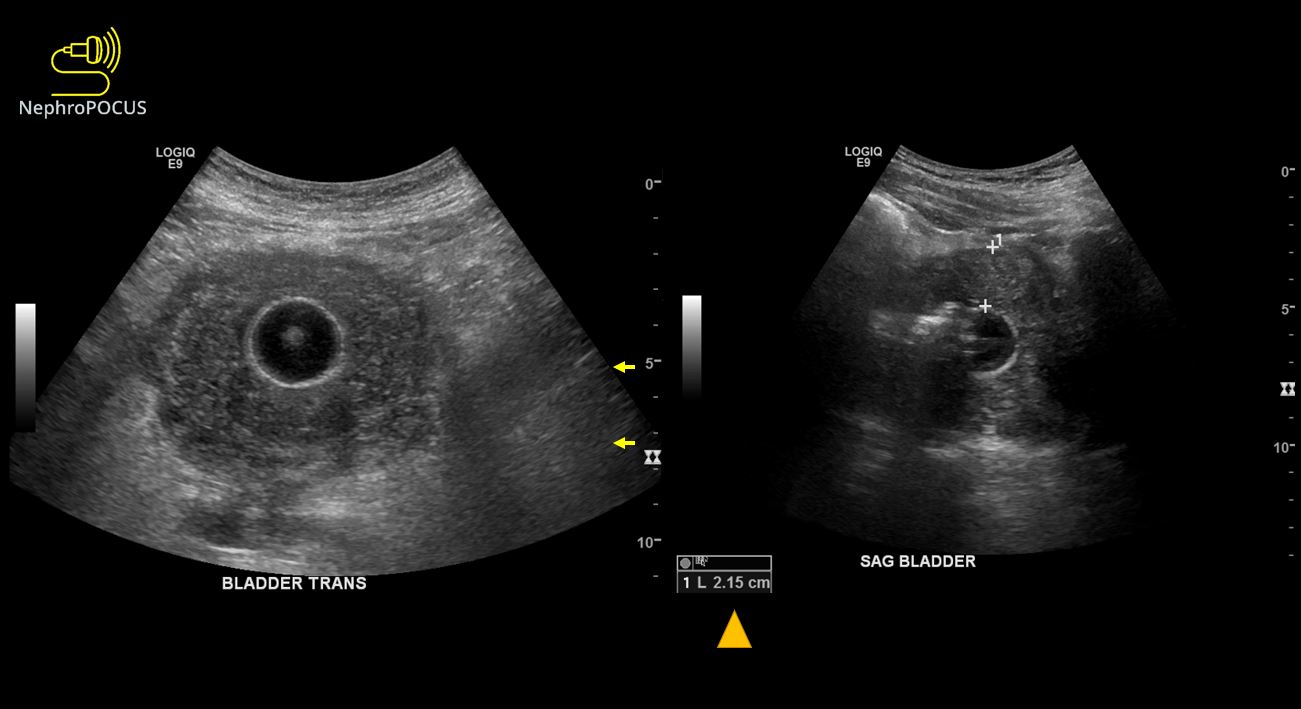

From nephropocus.com

Urinary bladder wall thickness what is the number to remember What Does Mild Bladder Wall Thickening Mean I had thickening of my bladder wall when i was experiencing severe urine retention, where my bladder was forced to hold up to 1000. Bladder wall thickening, also known as bladder wall hypertrophy, refers to an abnormal thickening of the bladder's muscular layer. When that happens, it’s harder for. Bladder trabeculation happens when the walls of the bladder thicken, making. What Does Mild Bladder Wall Thickening Mean.

Urinary bladder wall thickness what is the number to remember What Does Mild Bladder Wall Thickening Mean When that happens, it’s harder for. There are several serious underlying conditions that could. Bladder wall thickening, also known as bladder wall hypertrophy, refers to an abnormal thickening of the bladder's muscular layer. Chronic inflammation can cause scarring and thickening of the bladder wall, making. Interstitial cystitis (ic) is a painful condition in which the bladder wall becomes irritated and. What Does Mild Bladder Wall Thickening Mean.